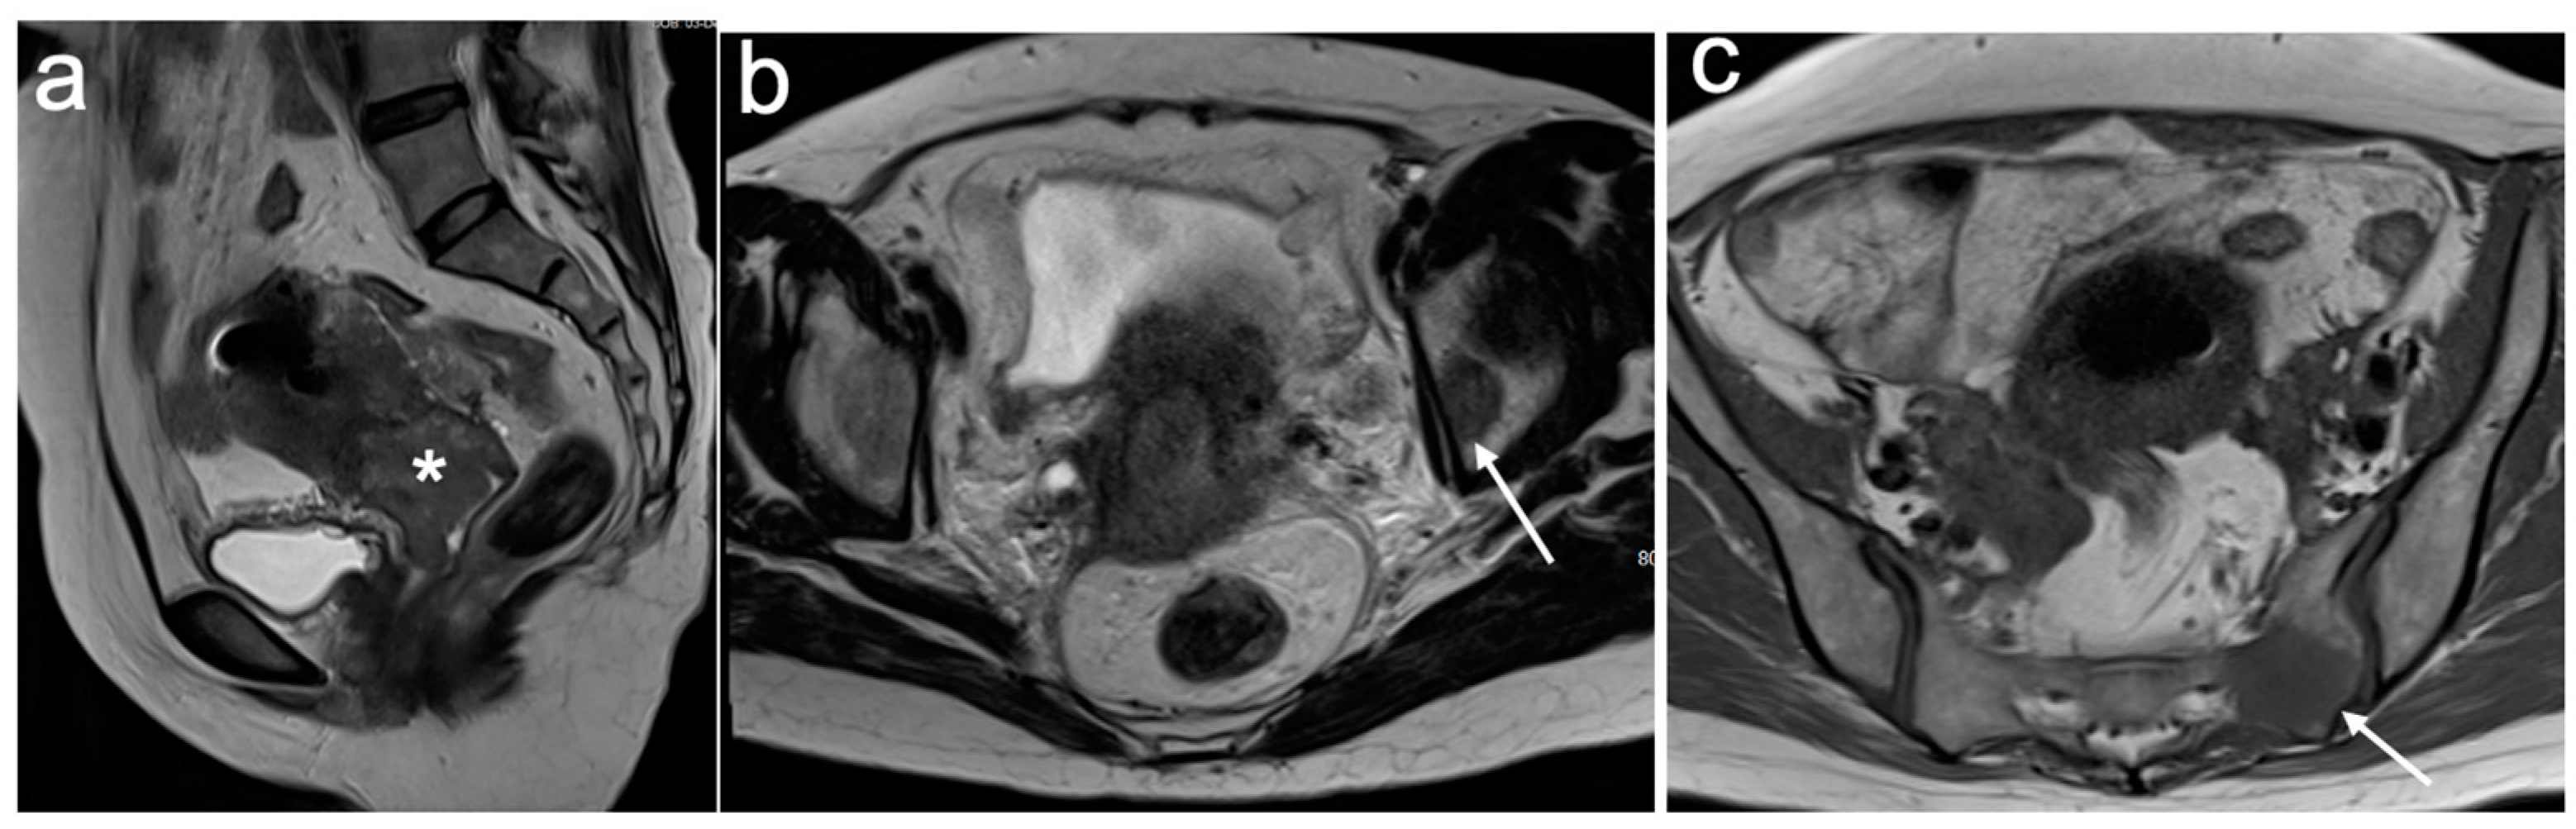

5. FIGO Stage II

6. FIGO Stage III

- Valentini, A.L.; Gui, B.; Miccò, M.; Giuliani, M.; Rodolfino, E.; Ninivaggi, V.; Iacobucci, M.; Marino, M.; Gambacorta, M.A.; Testa, A.C.; et al. MRI anatomy of parametrial extension to better identify local pathways of disease spread in cervical cancer. Diagn. Interv. Radiol. 2016, 22, 319–325. [Google Scholar] [CrossRef]

- Freeman, S.J.; Aly, A.M.; Kataoka, M.Y.; Addley, H.C.; Reinhold, C.; Sala, E. The revised FIGO staging system for uterine malignancies: Implications for MR imaging. Radiographics 2012, 32, 1805–1827. [Google Scholar] [CrossRef] [PubMed]

- Kostov, S.; Selçuk, I.; Watrowski, R.; Kornovski, Y.; Yalçın, H.; Slavchev, S.; Ivanova, Y.; Dzhenkov, D.; Yordanov, A. Pelvic Sidewall Anatomy in Gynecologic Oncology-New Insights into a Potential Avascular Space. Diagnostics 2022, 12, 519. [Google Scholar] [CrossRef]